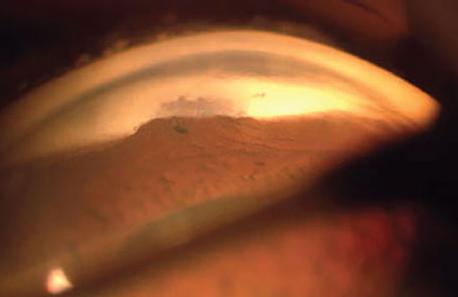

<여과포에서의 방수 누출, Leaking bleb>

1. 여과포에서부터 누출이 있으나, 전방의 깊이가 충분히 깊게 유지되며, 여과포에 염증이 없이 창백하면서 융기되어 있는 경우

우선 보존적으로 치료해볼수 있습니다.

대부분 안검의 운동에 의해서 스치면서 여과포에서 누출이 되기 때문에,

안검 운동을 막기위해서 연고를 넣고 압박 안대를 하면서 며칠간 지켜볼수 있습니다.